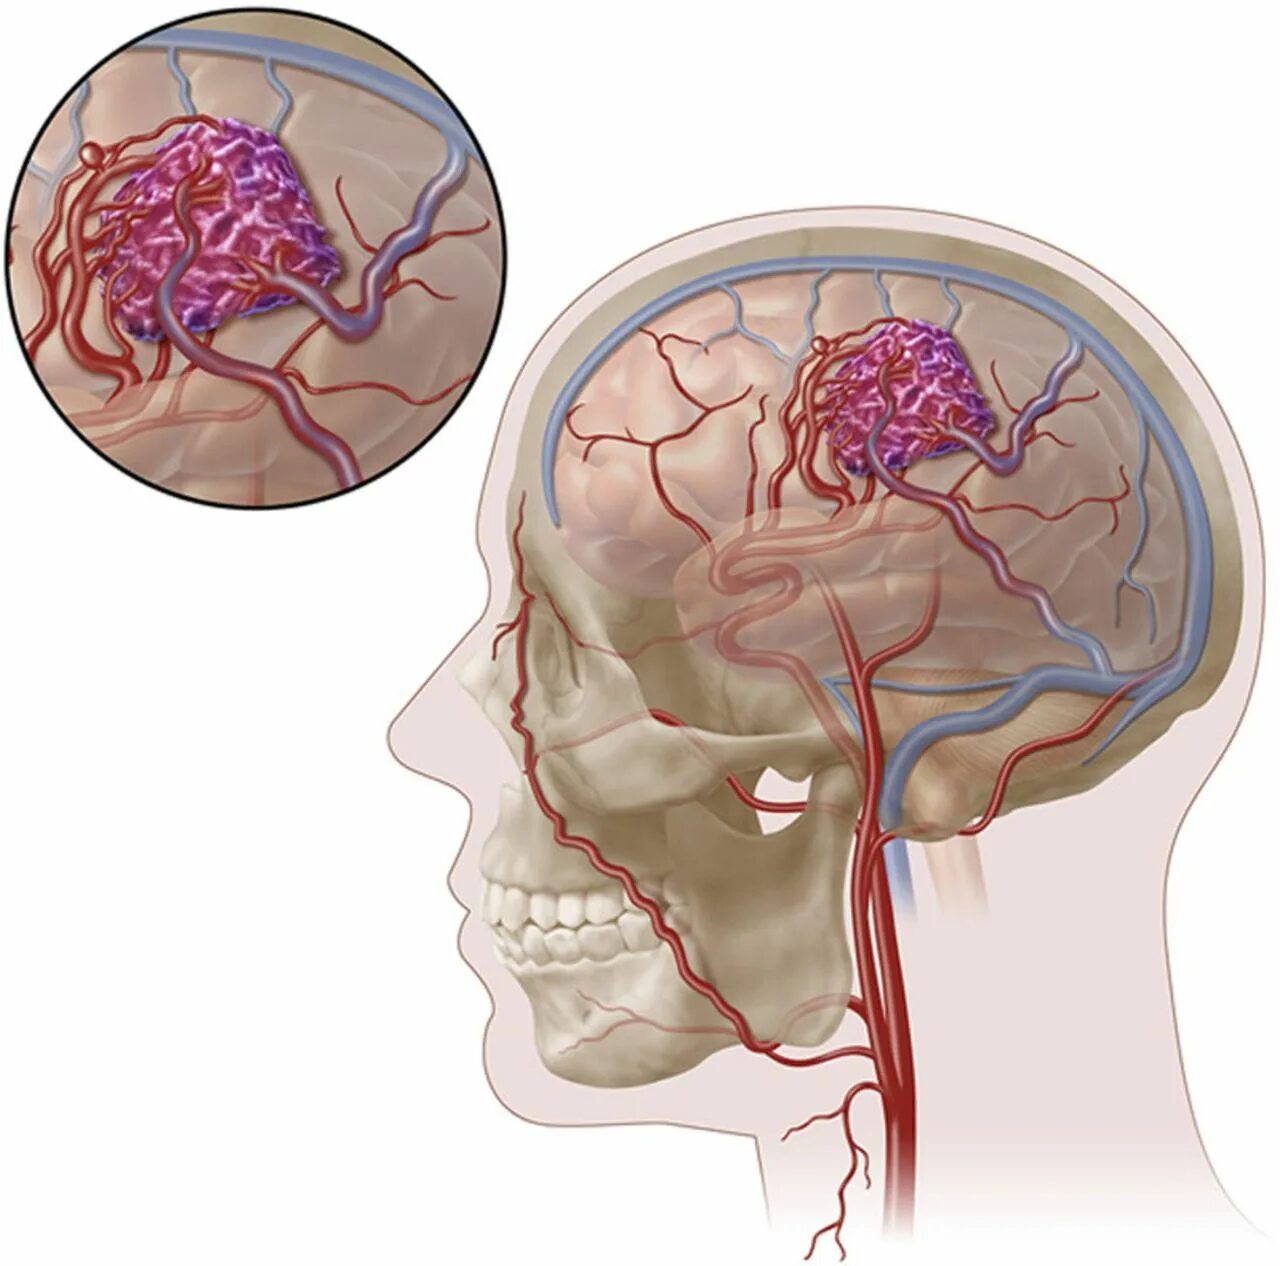

Мальформация сосудов